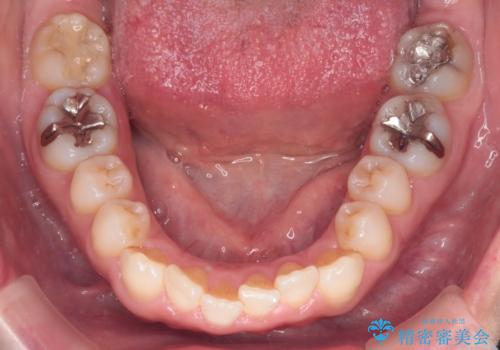

【インビザライン 】前歯のガタガタを治したい

- 前歯のガタガタを主訴に来院されました。

インビザライン で治療しました。途中は使用時間が20時間を切ることもありましたが、それでも頑張って使っていただき1年半で矯正終了することができました。